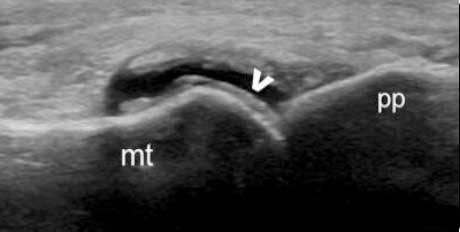

“双轨征”

跖趾关节软骨表面可见高回声不规则增强的软骨滑膜边缘线,呈“双轨征”。

高回声带

软骨表面回声增强,与深面的骨性关节面强回声线形成“双轨征”。

聚集体

髁软骨的双轨征状,显示髌腱内部的聚集体